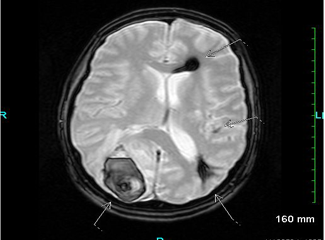

A 59-year-old woman with chronic hepatitis C presented with abdominal pain. She received warfarin for portal vein and superior mesenteric vein thrombosis and developed a severe headache with nausea, vomiting, and right-sided weakness. CT of the brain showed left frontoparietal intracranial bleeding. Warfarin was discontinued. Routine abdominal ultrasonography for hepatoma surveillance found new infiltrative liver lesions. Biopsy revealed hepatocellular carcinoma. The patient was referred for tumor embolization. Before the start of treatment, the patient developed severe right-sided headache, nausea, and vomiting, with visual field defect. Emergency CT of the brain revealed a hemorrhagic lesion in the right superior parietal lobe cortex/subcortex. MRI of the brain revealed a right posterior parietal lobe hematoma. Gradient echo MRI showed a small focus of low signal intensity in the left parietal subcortical white matter.